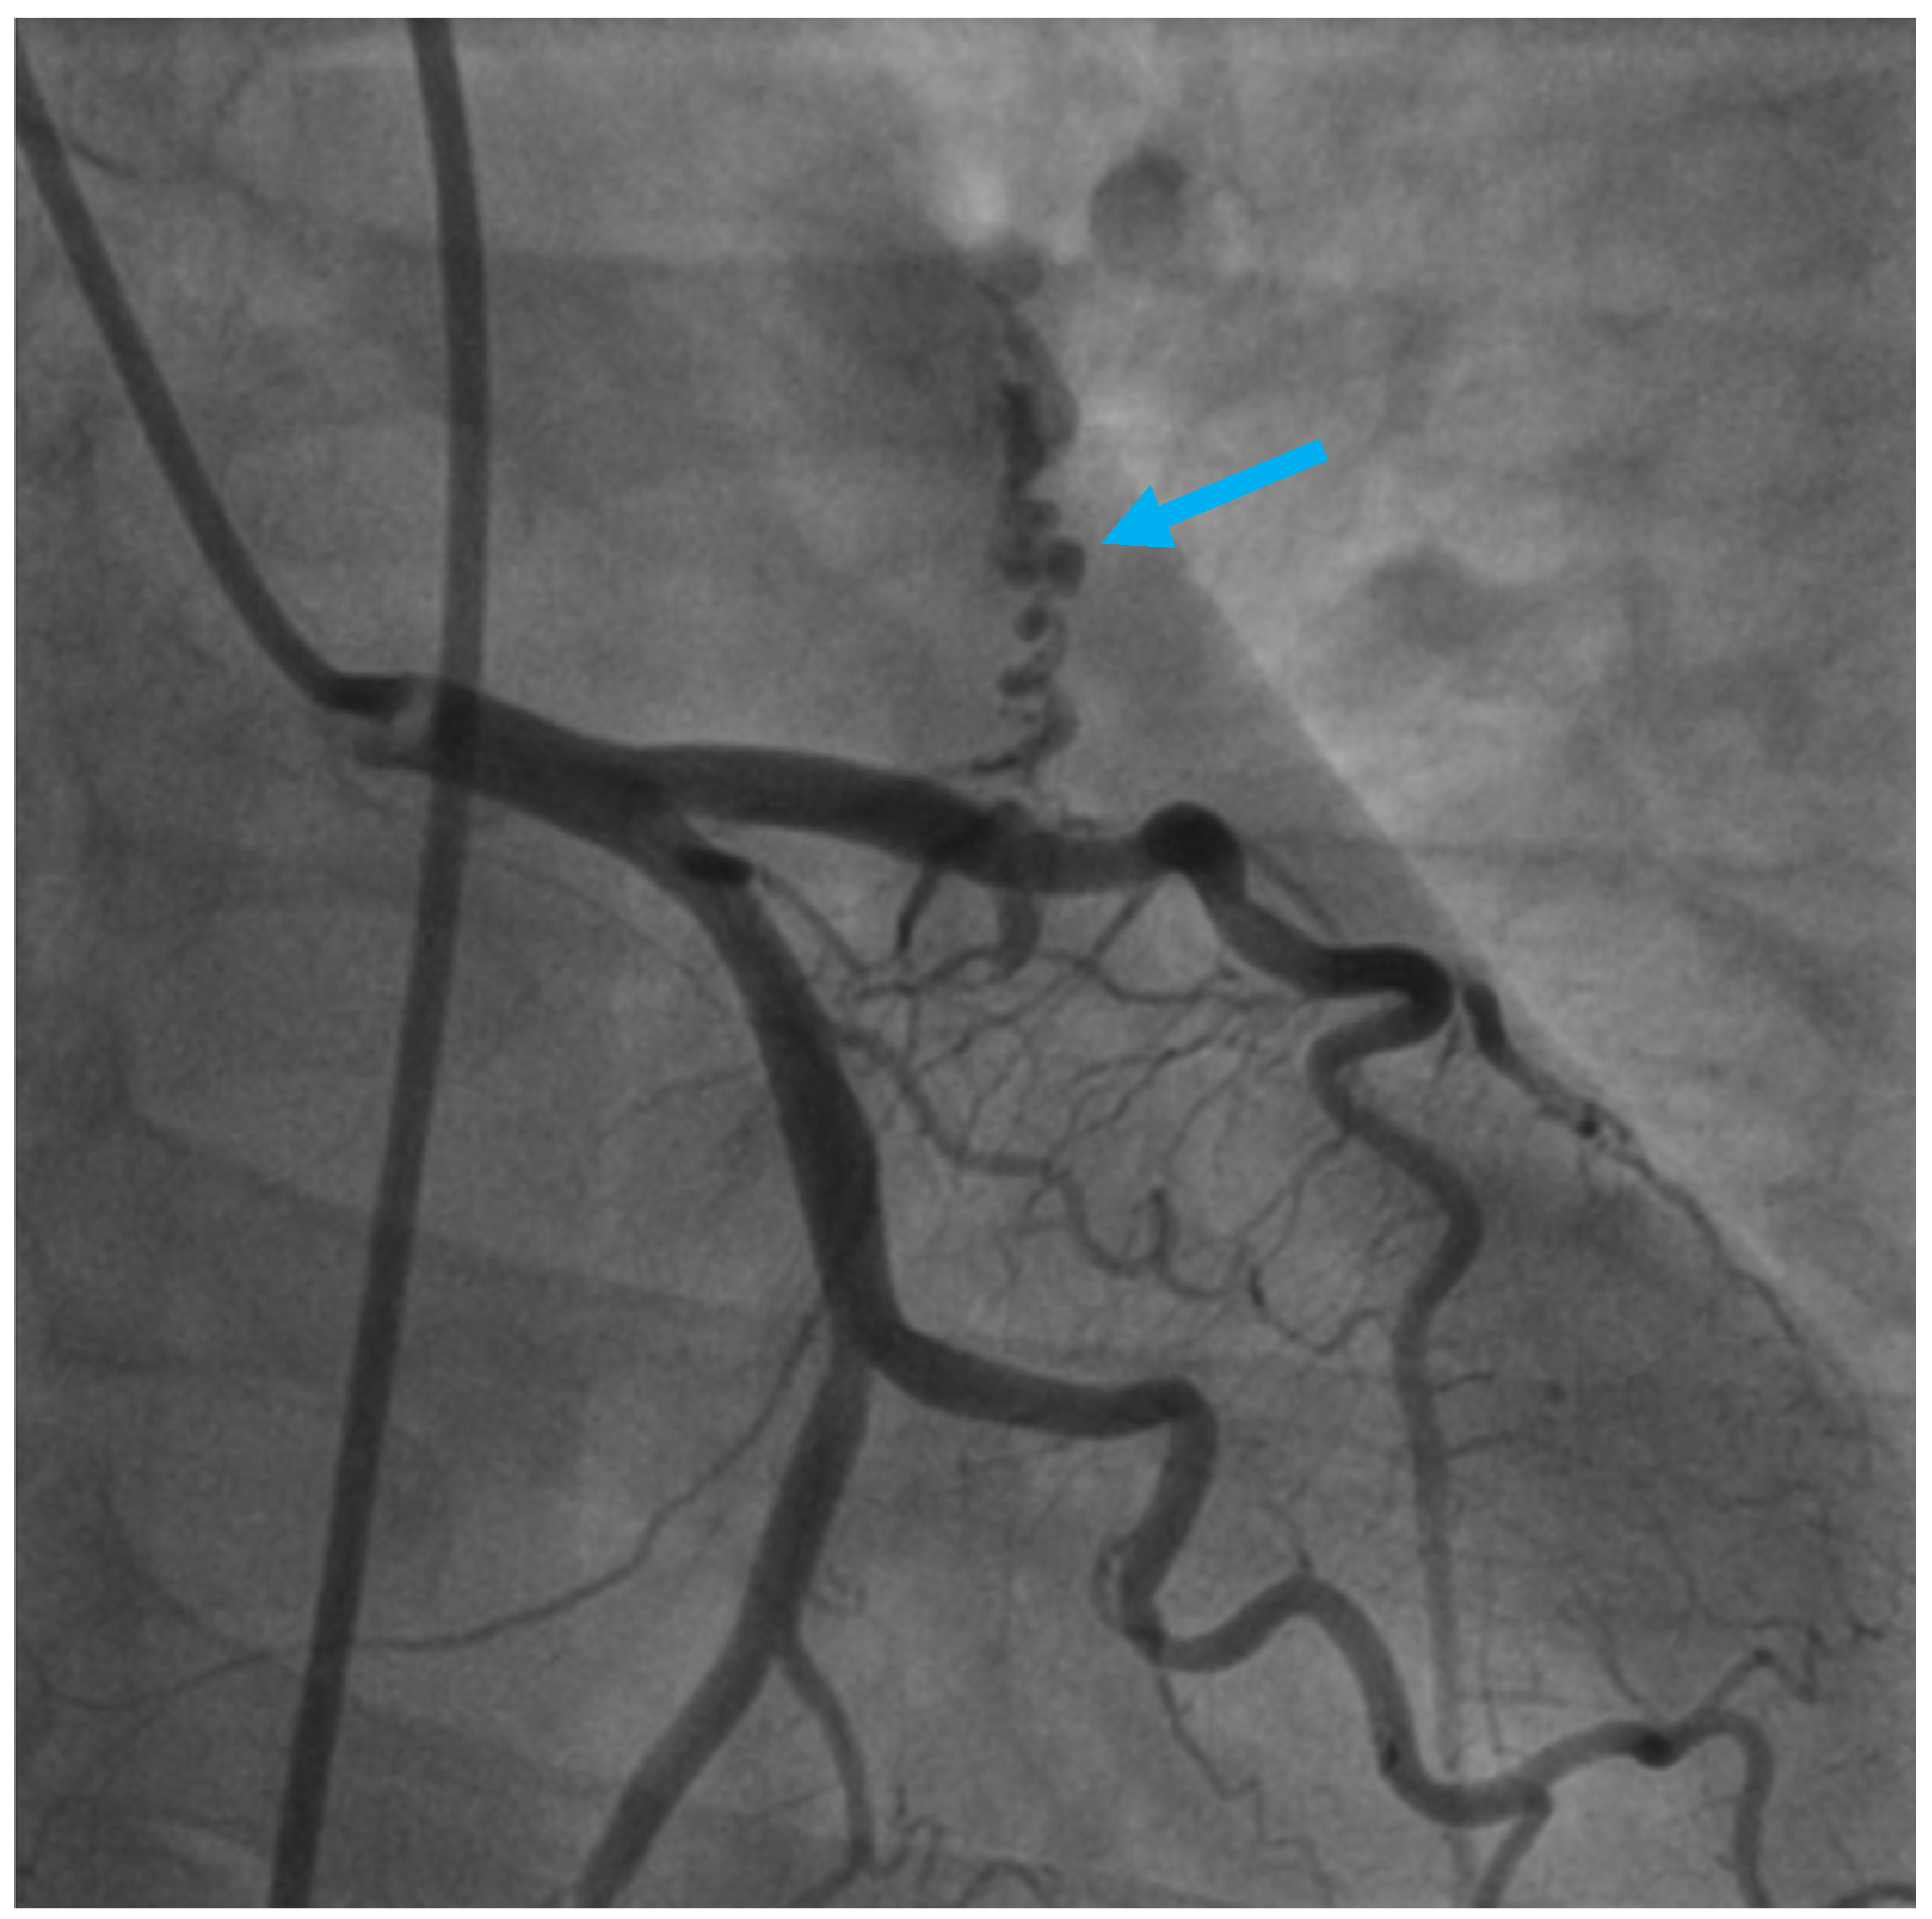

A Rare Case of Left Anterior Descending Coronary Artery to Pulmonary Trunk Fistula Associated with Takotsubo Cardiomyopathy